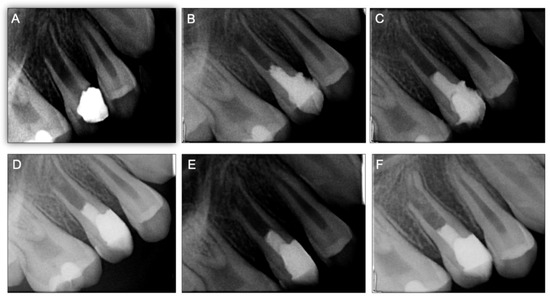

After REPs, the tooth (15) was asymptomatic without signs of coronal discoloration. Follow-up was successively performed at 3, 6, 12 months, 3 years, and 5 years (Figure 1E,F and Figure 2). The radiographic evaluation depicted a continuity of the periodontal ligament space (confirming the absence of an apical radiolucency) as well as an appreciable increase in the root length and thickness. With the progression in time of follow-up, the partial separation of the apical root portion observed at 3, 6, and 12 months decreased significantly compared to the 2- and 5-year follow-up X-rays. After 5 years, a fully developed root structure was observed at the periapical radiography, and on the cone-beam computed tomographic (CBCT) scan (Supplementary materials: Video S1A, S1B), with an increase in length and thickness of the root walls as well as a decrease of the root canal lumen width.

Figure 2. Case report 1 with controls radiographic images: (A) 12-month postoperative periapical radiograph control of tooth the continuity of the periodontal ligament space with absence of apical radiolucency was observed at radiographic evaluation showed appreciable root length increase; (B) after 2 years; (C) a total root formation is observed in radiographs after 3-years; (D) at the 5-year follow-up, an increase was observed in the root length and thickness and a decrease of the root canal lumen width.